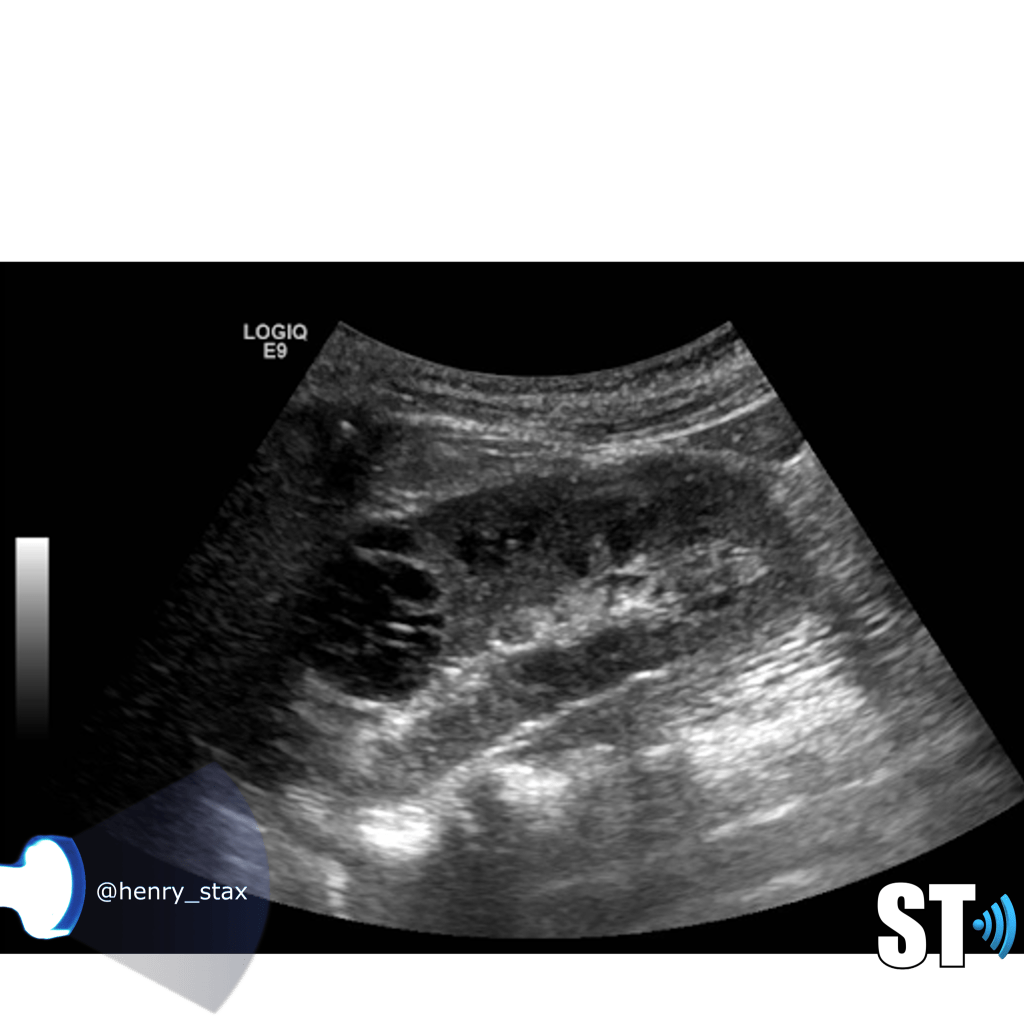

Renal Cystic Disease

Renal cysts are very common and as a sonographer you’ll encounter them frequently in the pediatric and adult populations. Approximately 50% of people who are 50 years and older have simple kidney cysts. The majority of parenchymal cystic lesions are simple epithelial cysts. They have thin walls, are anechoic, good through transmission. They can have thin septations or internal debris(5%) these may require follow up. Chronically some can develop calcifications on their walls.

Simple cysts

Cysts are non functioning parts of the kidney. Simple cysts typically pose no health problems. Simple cysts are often found incidentally when the patient is undergoing a procedure for some other complaint. To meet the criteria for cysts the lesion should be

- Round or oval

- Thin wall

- Anechoic

- Good through transmission (posterior acoustic enhancement)